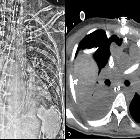

CT and chest

radiography in evaluation of mechanical circulatory support devices for acute heart failure. Malposition of Impella device. AP Chest radiograph with CLAHE filter (a) demonstrates a left ventricle Impella device with its tip projecting over the left ventricle (black arrow). Axial contrast enhanced CT (b) demonstrating the pigtail portion of the Impella device is entangled within the papillary muscle apparatus (black arrow). This finding is not detected on radiograph but can be identified on a CT. (CLAHE—contrast limited adaptive histogram equalization)